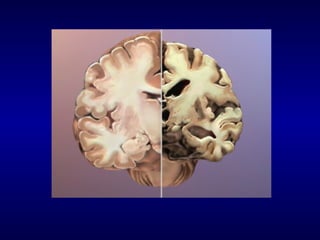

DOENÇA DE ALZHEIMER

Déficits proeminentes de memória,

frequentemente a queixa principal ,

seguidas de déficits de iniciativa e

visuoespacial

Dificuldade de encontrar palavras ,

compreensão, fala vazia.

Dificuldade de julgamento, abstração,

funções executivas (não consegue avaliar

riscos)

CURSO CLÍNICO DA DA

Deterioração cognitiva progride e afeta

todas as áreas da cognição

Aivds pioram progressivamente (dirigir,

telefonar, fazer o banco)

Nas fases moderadas a severas o

paciente não realiza Avds.

No estágio final a doença compromete

todas as funções cerebrais